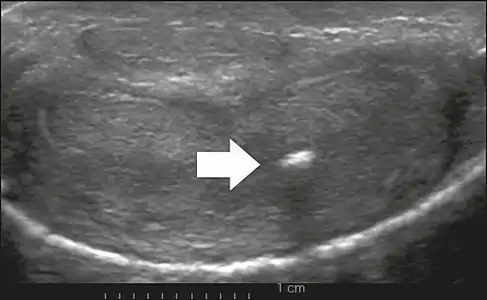

Venous drainage is performed by the deep and superficial dorsal veins of the penis. The dorsal arteries of the penis are located adjacent to the deep dorsal vein and a cavernous artery is located in the center of each corpus cavernosum. On color Doppler, the cavernous arteries present single phase flow. In the flaccid penis (Figure 3), the normal cavernous arteries show a systolic peak between 11 and 20 cm/s. At the beginning of erection, the systolic and diastolic flows undergo progressive increases. When vein occlusion begins, the diastolic flow decreases progressively, and once stiffness is established, it becomes negative.[1]

Figure 3: Longitudinal, ventral ultrasound of the penis, with pulsed mode and color Doppler. Normal flow pattern of the cavernous artery in a flaccid penis.[1]